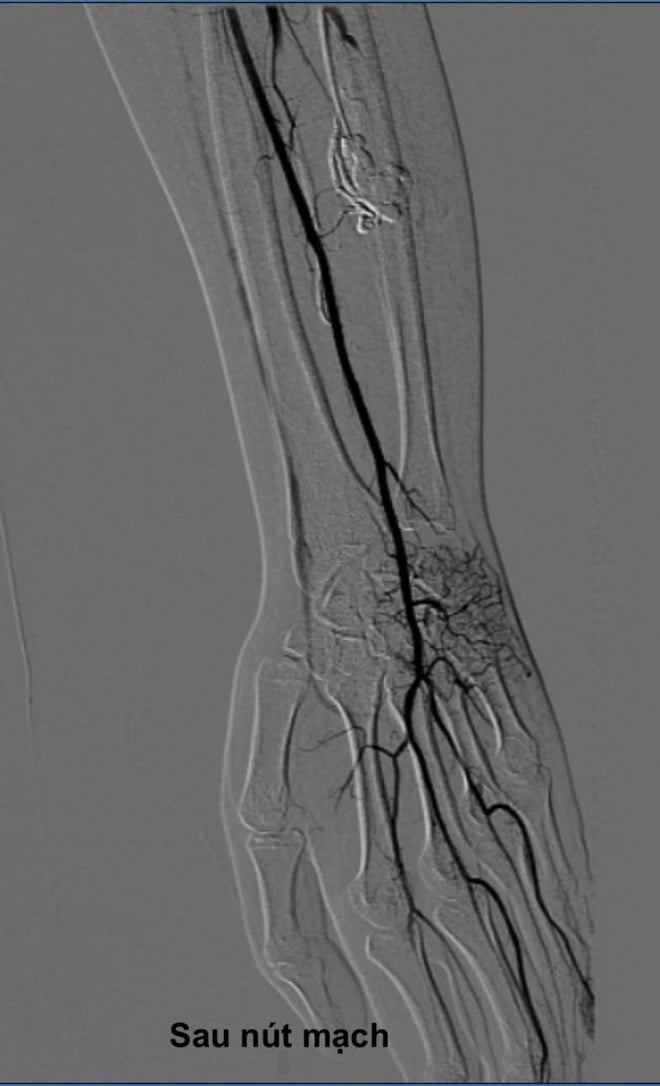

បន្ទាប់ពីការពិគ្រោះដោយប្រុងប្រយ័ត្ន វេជ្ជបណ្ឌិតបានសម្រេចចិត្តមិនធ្វើការវះកាត់បើកចំហបែបប្រពៃណីទេ ប៉ុន្តែដើម្បីធ្វើការវះកាត់បំប្លែងពន្លឺតាមរន្ធគូថសម្រាប់អ្នកជំងឺ LQ ដែលជាបច្ចេកទេសវិទ្យុសកម្មទំនើប និងរាតត្បាតតិចតួចបំផុត។

ក្រោមការណែនាំរបស់ម៉ាស៊ីន Digital Subtraction Angiography (DSA) វេជ្ជបណ្ឌិតប្រើម្ជុលតូចមួយដើម្បីចាក់ដោយផ្ទាល់តាមស្បែក ចូលទៅក្នុងសំបុកដែលខូចទ្រង់ទ្រាយដែលស្ថិតនៅជ្រៅក្នុងសាច់ដុំកំភួនដៃ។ បន្ទាប់មក អេតាណុលដាច់ខាតត្រូវបានចាក់តាមម្ជុលដើម្បីស្កូរ៉ូស និងបិទសរសៃឈាមមិនប្រក្រតីទាំងស្រុង។

នីតិវិធីទាំងមូលចំណាយពេលប្រហែលមួយម៉ោង។ អ្នកជំងឺភ្ញាក់ខ្លួនពេញទំហឹង ហើយមិនបានធ្វើការវះកាត់ដោយចំហទេ។

ភ្លាមៗបន្ទាប់ពីការអន្តរាគមន៍ ភាពខុសប្រក្រតីត្រូវបានផ្សាភ្ជាប់ ហើយលំហូរឈាមធម្មតាត្រូវបានស្តារឡើងវិញ។ បន្ទាប់ពីពីរបីថ្ងៃ រោគសញ្ញានៃការឈឺចាប់ និងស្ពឹកនៅក្នុងម្រាមដៃរបស់អ្នកជំងឺ Q. ត្រូវបានកាត់បន្ថយយ៉ាងខ្លាំង។